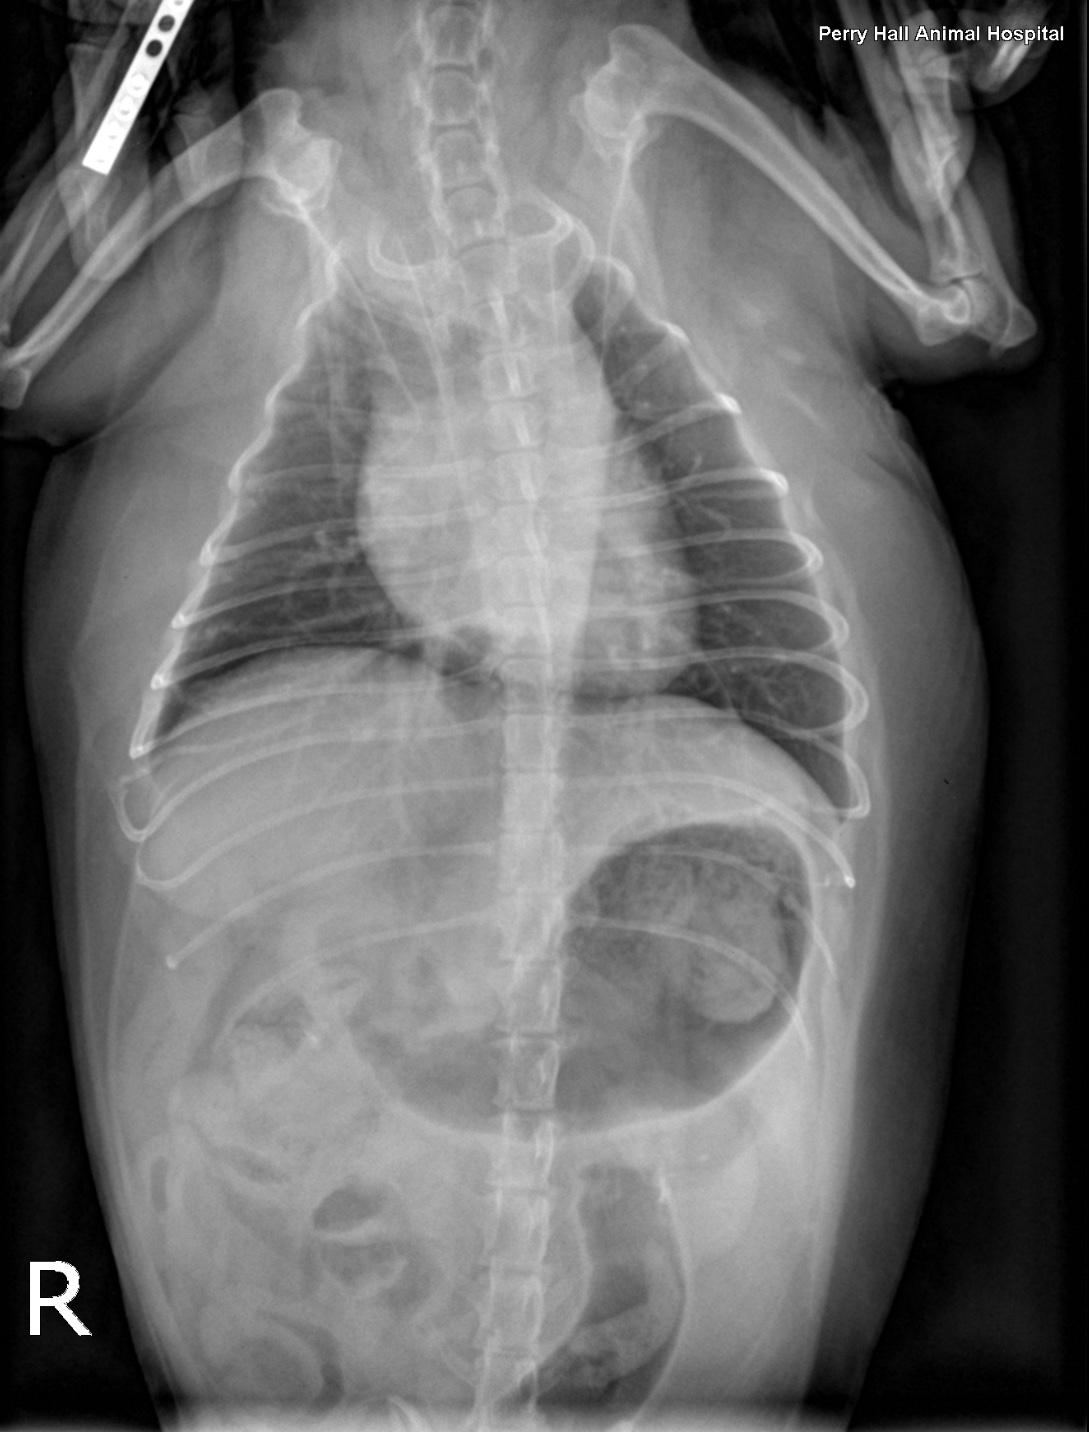

Rads- Left lateral, right lateral and VD views of the thorax and neck. One of the lateral views was obtained in fair inspiration (degree of inspiration reduced as a function of the disease), one was an expiratory view. There was mild to moderate rotation of the trunk in the lateral views. There was superimposition of the front limbs with the cranial thorax. The hands of the holding person were in the primary beam during exposure which is strictly prohibited.

Extrathoracic soft tissue structures: The stomach was moderately distended with gas and food. The liver extended beyond the costal arch and mild lobar rounding was noted. There was a multilobulated soft tissue swelling with mass effect caudoventral to the mandibles.

Intrathoracic structures: The chest volume was small. There was an intrathoracic tracheal collapse and collapse of the main stem bronchi on the expiratory view. The height of the trachea was reduced by more than 50 % as compared with the inspiratory view. The tracheal lumen was reduced to a height of 2mm level with the thoracic inlet when collapsed. The cardiac silhouette was normal for size and shape. The major vessels were within normal limits. The pulmonary vessels and caudal vena cava were within normal limits. No mediastinal widening was noted.

The radiographic findings are compatible with dynamic tracheal and bronchial collapse likely due to bronchomalacia.